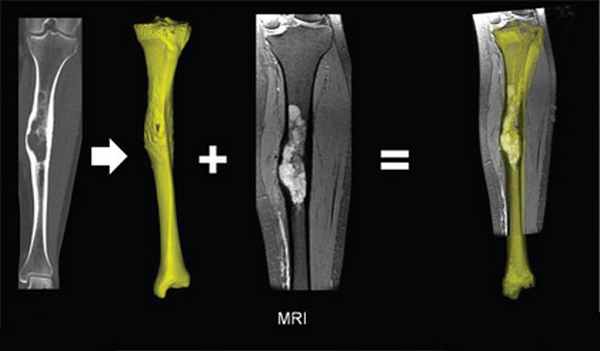

При помощи спиральной компьютерной томографии (СКТ): диагностирует в большинстве случаев. На срезах хорошо видна опухоль, ее «сетчатая» структура, хорошо различаются утолщенные костные балки, уплотнение кости по контуру гемангиомы.